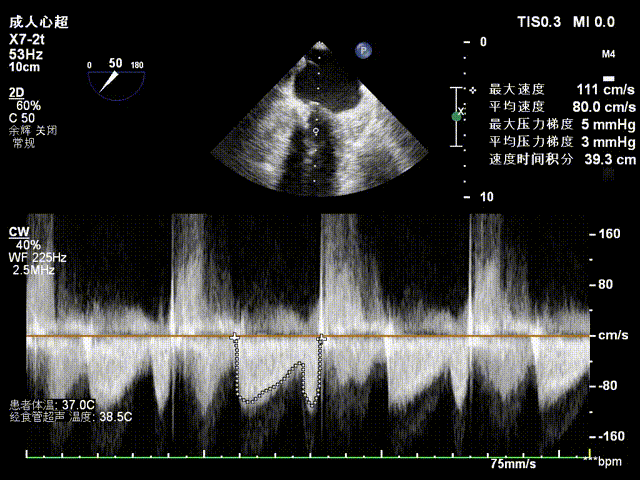

检查示组织桥明显,夹合器稳定,残余反流明显减少,降低至1+等级,二尖瓣平均跨瓣压差为3mmHg,经团队评估,手术效果达既定预期,各项指标平稳,顺利结束手术。

术后压差评估